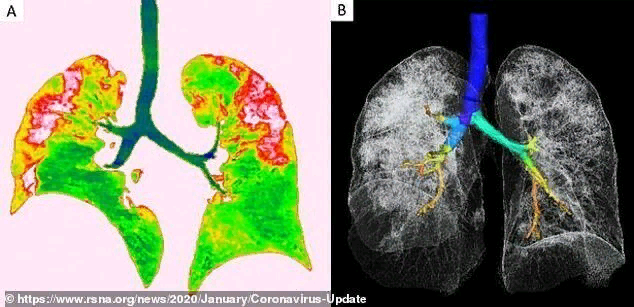

Шокирующие рентгеновские снимки 44-летнего пациента из Китая, умершего от коронавируса, показывают, что эта болезнь делает с человеческими легкими. Перед нами самое опасное осложнение вируса, переходящего в тяжелую пневмонию. Опубликованы рентгеновские снимки и компьютерная томография 44-летнего китайского пациента. По ним хорошо видно, как именно вирус разрушает легочную ткань. По утверждениям медиков, повреждения похожи на те, что обнаруживались в легких жертв атипичной пневмонии и ближневосточного респираторного синдрома. Рентгеновские снимки и томограммы легких 44-летнего пациента, умершего от коронавируса, были представлены китайскими врачами. Они дают подробную картину того, как вирус разрушает легкие человека. На снимках видны белые пятна в нижних отделах легких. Медики называют их «субплевральными уплотнениями по типу матового стекла». В этих областях воздушные пузырьки легких частично заполнены содержимым. Похожие поражения наблюдались также у пациентов с атипичной пневмоние